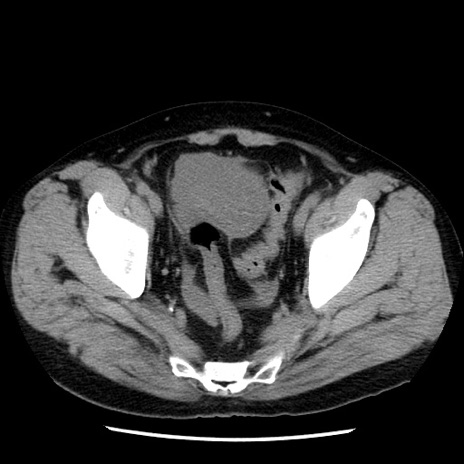

症例29(横断像)

【症例】40歳代男性

【現病歴】2日前から胃痛あり。徐々に周期的な激痛に変化した。本日になっても激痛があるため受診。

【身体所見】意識清明、BT 38-39℃台あり、腹部:膨満、やや硬、右下腹部に圧痛あり。

【データ】WBC 8500、CRP 23.26